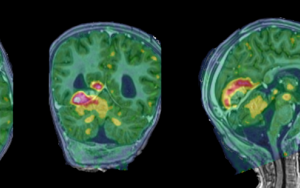

Stellenbosch University leads groundbreaking research project in paediatric Tuberculous meningitis

In a groundbreaking endeavour, an ambitious new research project (iThemba) was recently launched at Tygerberg Children's Hospital in collaboration with the...